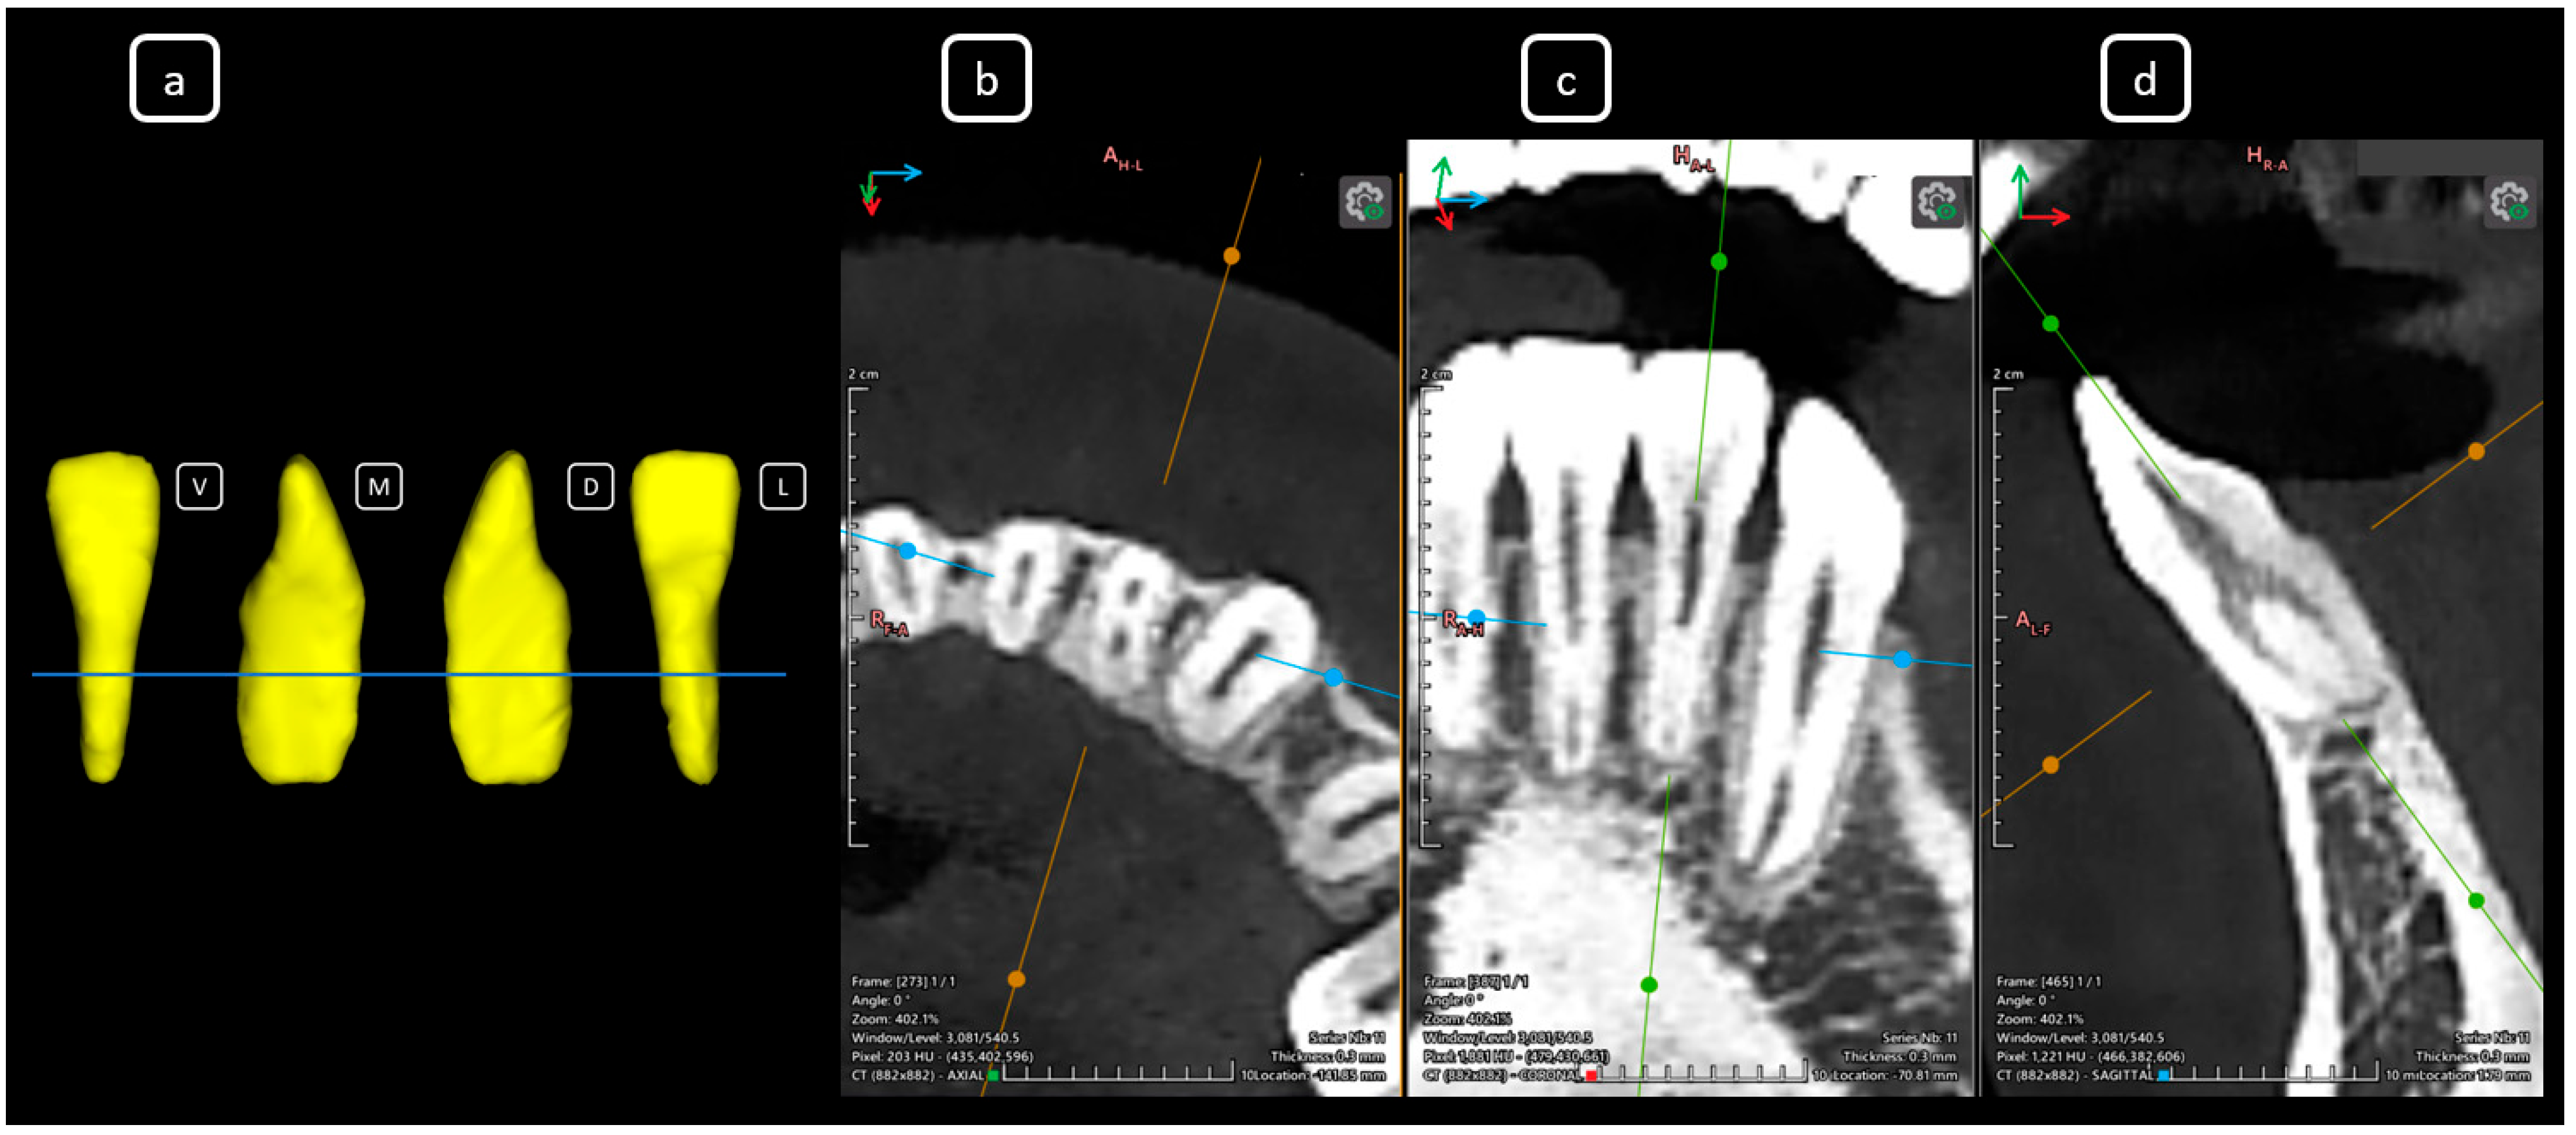

Imaging Findings of Clinical Significance in Endodontics During Cone Beam Computed Tomography Scanning of the Upper Airway—The Anterior, Bilateral, C-Shaped, Dual of Mandibular Root Canals: A Brief Case Report

García-Torres, E.; Guerrero-Falcón, D.L.G.; Bojórquez-Armenta, H.A.; Almeda-Ojeda, O.E.; Barajas-Pérez, V.H.; Solís-Martínez, L.J. Imaging Findings of Clinical Significance in Endodontics During Cone Beam Computed Tomography Scanning of the Upper Airway—The Anterior, Bilateral, C-Shaped, Dual of Mandibular Root Canals: A Brief Case Report. Diagnostics 2025, 15, 3157. https://doi.org/10.3390/diagnostics15243157